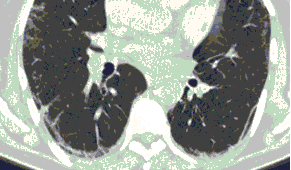

КТ имеет высокую чувствительность в выявлении изменений в легких, характерных для COVID-19. Применение КТ целесообразно для первичной оценки состояния ОГК у пациентов с тяжелыми прогрессирующими формами заболевания, а также для дифференциальной диагностики выявленных изменений и оценки динамики процесса. КТ позволяет выявить характерные изменения в легких у пациентов с COVID-19 еще до появления положительных лабораторных тестов на инфекцию с помощью МАНК. В то же время, КТ выявляет изменения легких у значительного числа пациентов с бессимптомной и легкой формами заболевания, которым не требуется госпитализация. Результаты КТ в этих случаях не влияют на тактику лечения и прогноз заболевания при наличии лабораторного подтверждения COVID-19. Поэтому массовое применение КТ для скрининга асимптомных и легких форм болезни не рекомендуется. При первичном обращении пациента с подозрением на COVID-19 рекомендуется назначать КТ только при наличии клинических и инструментальных признаков дыхательной недостаточности (SpO2 < 95%, ЧДД > 22).

4. Все выявляемые при лучевых исследованиях признаки, включая КТ-симптомы, не являются специфичными для какого-либо вида инфекции и не позволяют установить этиологический диагноз. Вне клинической (эпидемической) ситуации они не позволяют отнести выявленные изменения к пневмонии COVID-19 и дифференцировать их с другими пневмониями и невоспалительными заболеваниями. Данные лучевого исследования не заменяют результаты обследования на РНК SARS-CoV-2. Отсутствие изменений при КТ не исключает наличие COVID-19 и возможность развития пневмонии после проведения исследования.

15. Рекомендации по формированию описаний и оценке изменений в легких и ОГК при имеющейся/подозреваемой пневмонии COVID-19 представлены в Приложении 1.